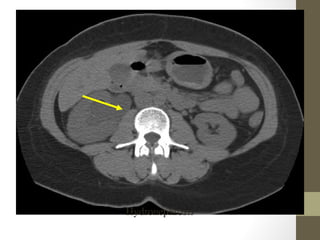

Radiology- CT Scan

diverticulitis, abscess, mesenteric ischemia, masses, obstruction

Kidney Stones- CT

Style

Sigmoid Tumor/Intussusception

Psoas Abscess

Retroperitoneal Abscess

TOA

Radiology- CT Scan •Detect leaking AAA (in stable patient) • Evaluate for renal calculi, appendicitis, perforation (free air), diverticulitis, abscess, mesenteric ischemia, masses, obstruction • Sensitivity and specificity vary • Not a place for unstable patients • Contrast • PO and IV contrast in most patients • sometimes rectal contrast is helpful to look for large bowel problems (appendicitis) • In patients with renal insufficiency • give IV contrast judiciously in patients • consider ultrasound as an alternative if possible • a creatinine > 1.5 usually requires bicarbonate and fluid hydration to minimize contrast nephropathy